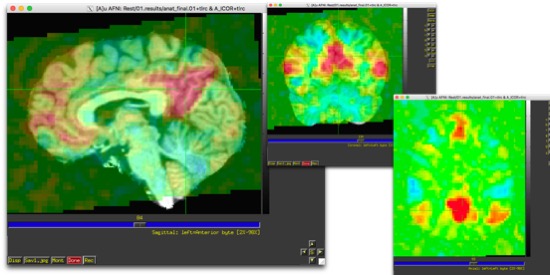

Now, we're going to start by finding the DMN. It's one of the most robust resting state networks, so if you can't find it in your processed data, there's a good chance something has gone horribly, horribly wrong. I find this by choosing a sagittal slice just off the midline (in about the center of that line of grey matter), and finding where the two marked sulci intersect. They have names, I don't remember what they are. But, it's a wiki page, so someone could add them. ctrl-shift-click.

Huzzah!! Now you should have a colored map over your anatomical set. And hopefully, it looks a lot like this:

There should be a big blob near where you clicked, and something else in the front. There shouldn't be that much outside the head. If you look at other views, it should be largely symmetric, and you should be able to clearly see 4 big blobs, which are generally visible in one axial slice. There should be a big blob where you clicked (there should always be a big blob where you put your seed- it should be strongly correlated to itself.) There should be two near the angular gyri, and one in the medial frontal lobes.

You can now ctrl-shift-click and drag. If you run along an axial or coronal slice, you should be able to see some largely symmetric blobs forming that more/less trace grey matter boundaries. If you pick out some areas of interest to you (motor system, visual system, etc), you should be able to see the rest of the network light up.